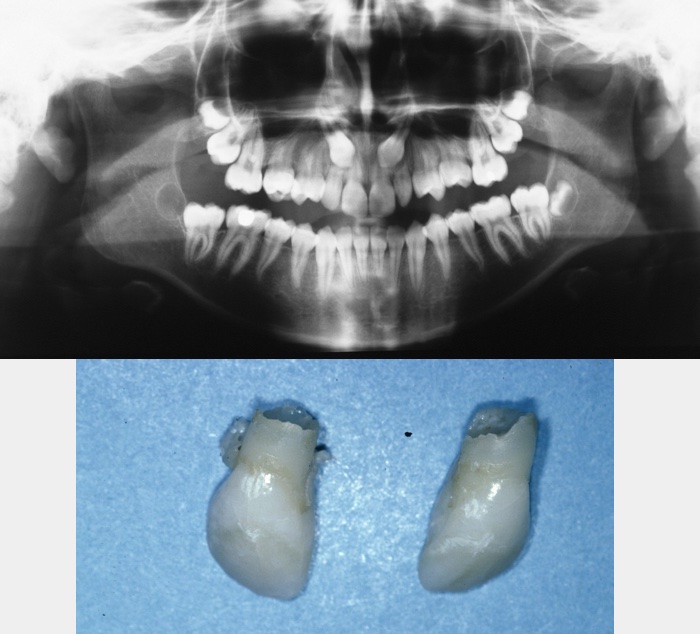

If failure of eruption is due to severe dilaceration, ankylosis or resorption (internal or external) then the only option is to extract the tooth. This should be undertaken in the same manner as for any unerupted tooth; accurate localization, adequate surgical exposure and careful removal. If the unerupted incisor(s) appear(s) of normal morphology with no obvious cause for their failure of eruption, then they should be exposed and given the opportunity to erupt.

Occasionally severe infraocclusion occurs. This is defined as when the marginal ridge of the primary tooth is below the level of the gingival margin. In these situations, the tooth should be extracted. These extractions are usually uneventful with the area of ankylosis not causing any significant problem. Occasionally, when the infraocclusion occurs early, the deciduous tooth totally submerges and not only prevents eruption of its successor but may cause adjacent teeth to tip towards the infraoccluded tooth, restrict development of the dentoalveolus (leading to lateral open bites), or, because of its continued communication with the oral cavity, may lead to decay, periodontal disease or periapical pathology. In these cases, it will be appropriate to remove the tooth and the technique employed will depend on accurate localization of the tooth by clinical and radiographic examination (Figure 11 and Figure 12).